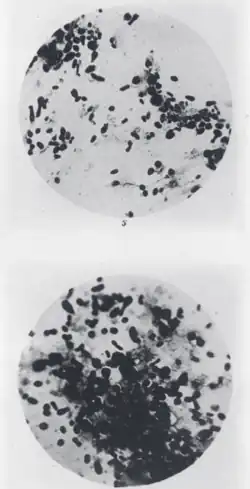

Researchers working in Asia during the "Third Pandemic" identified plague vectors and the plague bacillus. In 1894, in Hong Kong, Swiss-born French bacteriologist Alexandre Yersin isolated the responsible bacterium (Yersinia pestis, named for Yersin) and determined the common mode of transmission.[29] His discoveries led in time to modern treatment methods, including insecticides, the use of antibiotics and eventually plague vaccines. In 1898, French researcher Paul-Louis Simond demonstrated the role of fleas as a vector.[32]

The disease is caused by a bacterium usually transmitted by the bite of fleas from an infected host, often a black rat. The bacteria are transferred from the blood of infected rats to flea (Xenopsylla cheopis). The bacillus multiplies in the stomach of the flea, blocking it. When the flea next bites a mammal, the consumed blood is regurgitated along with the bacillus into the bloodstream of the bitten animal. Any serious outbreak of plague in humans is preceded by an outbreak in the rodent population. During the outbreak, infected fleas that have lost their normal rodent hosts seek other sources of blood.[33]